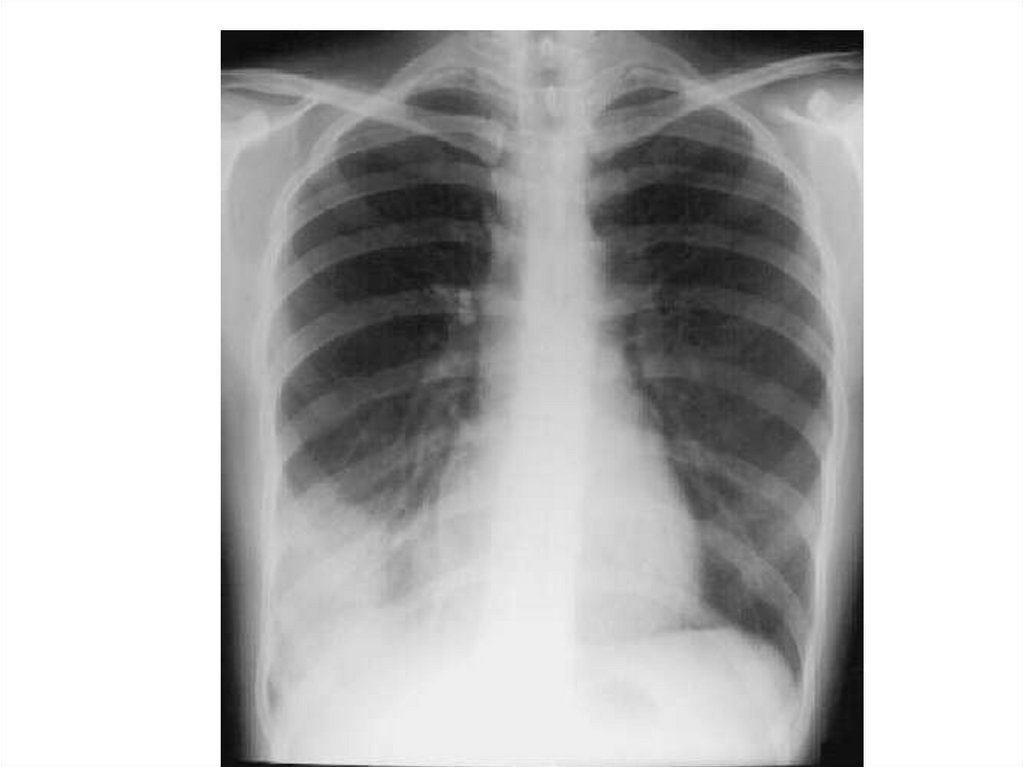

Абсцесс